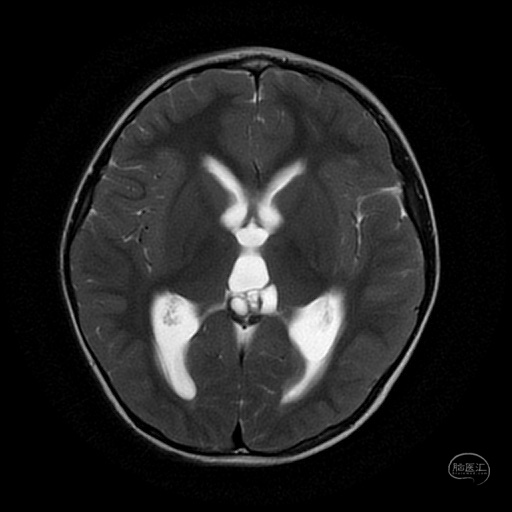

3岁男性患儿,间断头痛两个月入院,头部MR检查结果提示松果体区占位病变并梗阻性脑积水。

头部MR检查T2水平位显示松果体区囊实性占位病变,同时表现侧脑室及三脑室轻度扩张。